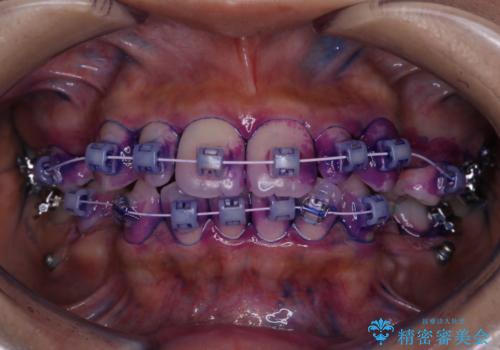

- 前歯の汚れが気になるため、綺麗にしたいとのことで来院されました。PMTC30分コースを行いました。

毎日丁寧に歯磨きをしていても、日常生活での飲食物などにより着色してしまうことはあります。PMTCでは、歯の表面の凸凹にミネラルを補給して、ツルツルの表面に仕上げます。定期的にPMTCを行うことにより、歯質の強化になり着色がつきにくい状態になります。

また、歯と歯の間に歯石がたまるとフロス・糸ようじなどが通らなくなってしまいます。定期的に機械的なクリーニングを行い健康的な歯肉の状態を保つことが大切です。